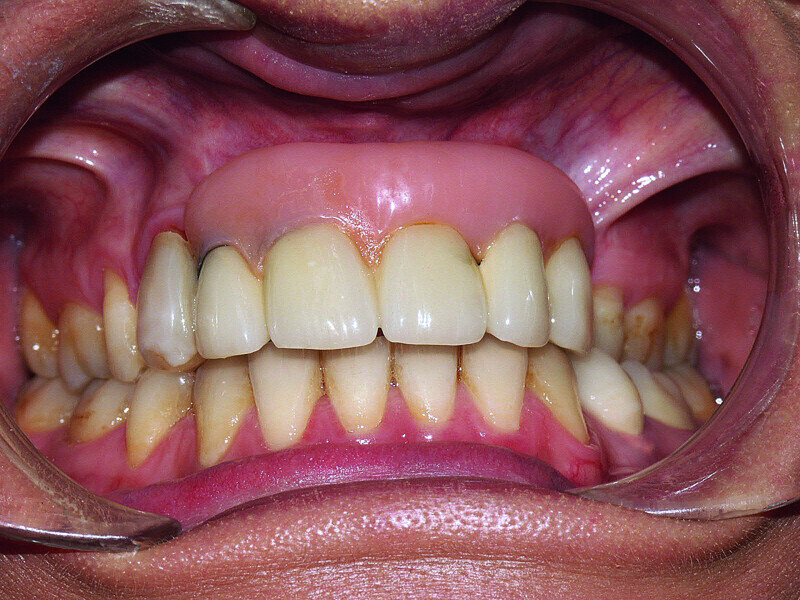

Fig. 38: Final cosmetic check-up showing correct lip support with the new extremely reduced false gingiva.

Fig. 39: Final cosmetic check-up showing correct lip support with the new extremely reduced false gingiva.